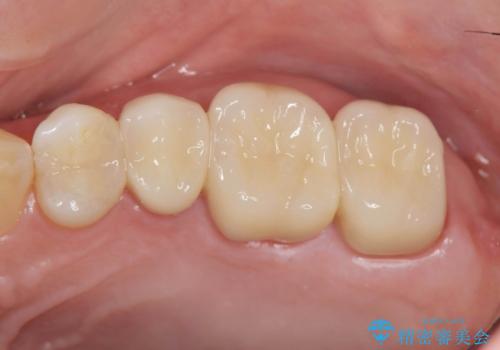

銀歯を丁寧に除去すると、銀歯の下で虫歯の再発やセメントの劣化が確認されたので、拡大鏡・マイクロスコープを用いて虫歯のみを丁寧に取り除いたのち、精密なセラミッククラウンの製作を進めます。

- 47.3万円(ジルコニアクラウン×3・仮歯×3・セラミックインレー×1)費用は治療当時の料金となります

拡大鏡・マイクロスコープを用いて虫歯を丁寧に除去することで、健全な歯質や神経を守ることにつながります。